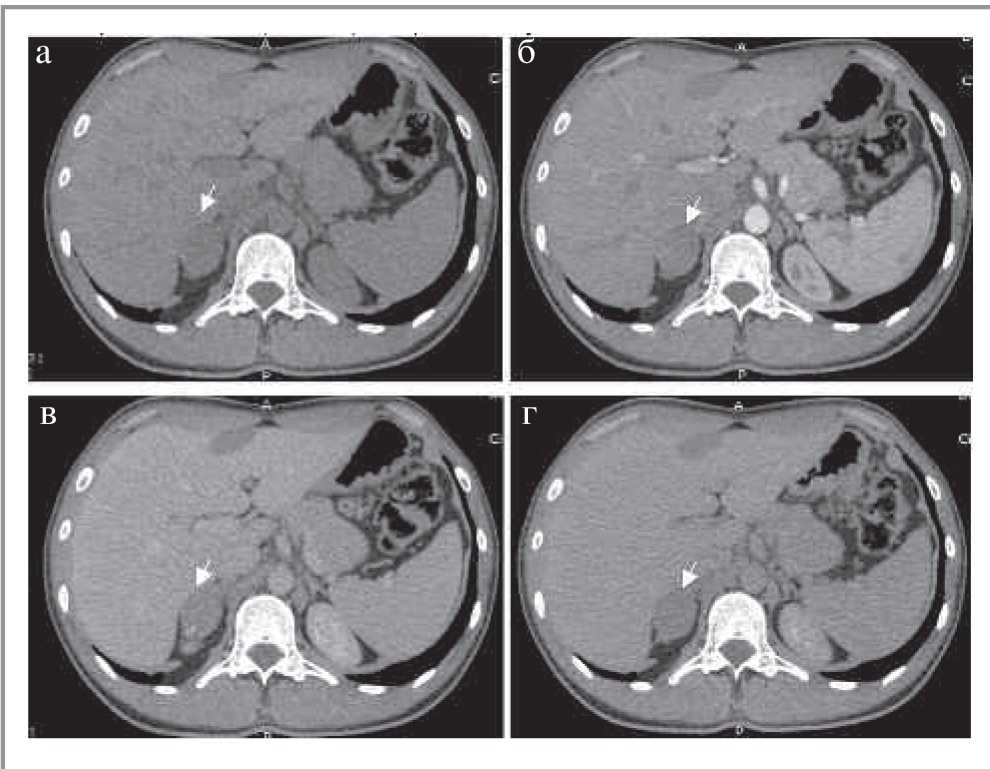

Как правило, АКР представляет собой крупное образование (от 2 до 40 см, в среднем 11–12 см) с неровными нечеткими контурами, повышенной плотности (более 10 ед. Н). При болюсном контрастном усилении образование умеренно неоднородно накапливает контрастный препарат со слабым его вымыванием в ОФ. Для данного образования характеры зоны некроза и кровоизлияний, а также кальцинаты, которые встречаются в 30% случаев [20]. При контрастировании возможно обнаружение тонкого капсулоподобного ободка контрастирования (рис. 7) [21]. Необходимо учитывать, что АКР также может быть выявлен в структуре таких доброкачественных образований, как аденомы (в структуре коллизионной опухоли); рис. 8.

Рис. 7. МСКТ, аксиальная проекция. Рак надпочечника. КТ-изображения в аксиальной проекции: а – НФ; б – АФ; в – ВФ; г – ОФ. В теле правого надпочечника определяется овальной формы образование (стрелка) с четкими ровными контурами, неоднородной структуры за счет наличия кальцинатов по периферии.

Рис. 8. МСКТ, аксиальная проекция. Коллизионная опухоль правого надпочечника (рак в структуре аденомы). КТ-изображения в аксиальной проекции: а – НФ; б – АФ; в – ВФ; г – ОФ. В правом надпочечнике определяется округлое образование (стрелка) пониженной плотности с четкими ровными контурами, неоднородной структуры за счет наличия центрально расположенного мягкотканного включения, интенсивно накапливающего контрастный препарат, со слабым его вымыванием в ВФ и ОФ.

Чаще поражается левый надпочечник, в то время как двустороннее поражение встречается менее чем в 10% случаев [20]. Для АКР характерны признаки злокачественности: инвазивный рост с вовлечением окружающих структур и органов или метастазы. Вовлечение почечной вены (9–19% наблюдений) чаще встречается при опухоли правого надпочечника и проявляется распространением опухоли в просвете данной вены, далее в нижней полой вене до правого предсердия [20]. Метастазы наиболее часто поражают легкие, печень, лимфатические узлы и кости.